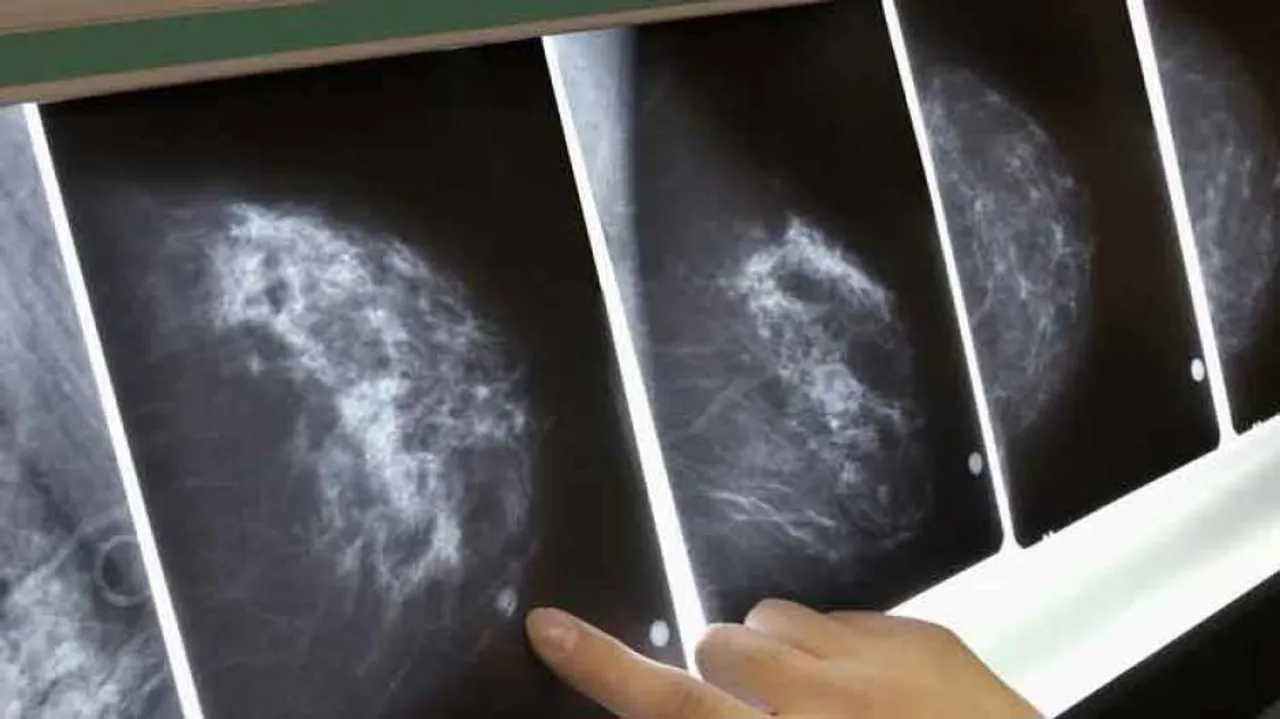

San Francisco: In a ray of hope for those who have to go for breast cancer screening and even for healthy women who get false alarms during digital mammography, an Artificial Intelligence (AI)-based Google model has left radiologists behind in spotting breast cancer by just scanning the X-ray results.

Reading mammograms is a difficult task, even for experts, and can often result in both false positives and false negatives.

Digital mammography or X-ray imaging of the breast, is the most common method to screen for breast cancer, with over 42 million exams performed each year in the US and the UK combined.